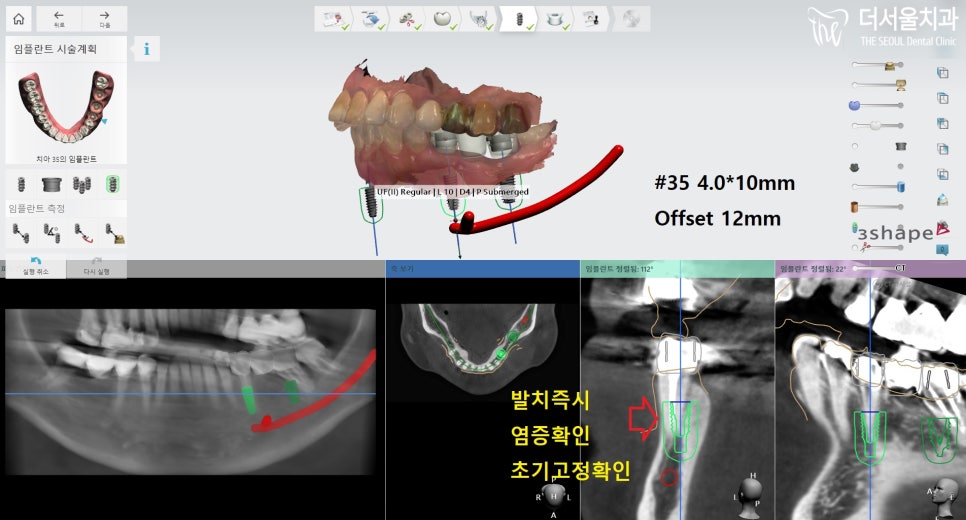

발치 전 컴퓨터 분석을 통해

임플란트 식립 계획을

수립하였는데요.

다행스럽게도 뼈이식을

진행하지 않아도 되었기에

발치 즉시 염증 확인 및

제거하는 과정이 필요했습니다.

의료진이 꼼꼼히 확인 후,

염증이 남아있지 않도록

소독을 통해 깔끔히 처리했습니다.